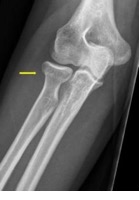

Een breuk in de radiuskop of radiushals komt vaak voor. De radiuskop of radiushals zit bij de elleboog, in het spaakbeen. Het spaakbeen is het bot tussen de pols en de elleboog.

- U heeft een kleine breuk in het spaakbeen ter hoogte van de elleboog.